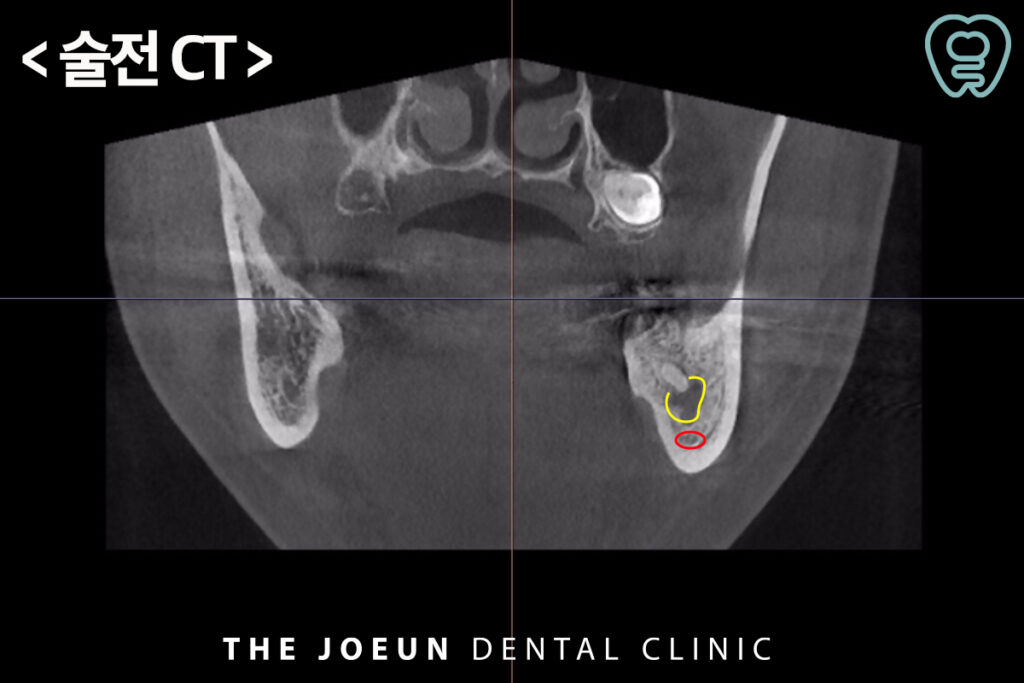

오늘은 신경관과 가까이 있는 치아 뿌리의 염증으로 인해 발치 후 충분한 기간을 기다려준 뒤 임플란트를 식립하신 환자분을 소개해 드리도록 하겠습니다. 환자분께서는 전체적인 검진을 위해 내원하셔서 왼쪽으로 식사를 하실 때 간혹 찝찝한 느낌은 있었지만 큰 불편함은 없으셨다는 말씀을 해주셨는데요.

파노라마를 확인해보니 왼쪽 아래 신경치료 후 크라운이 되어 있는 가장 안쪽 어금니의 뿌리에 커다란 염증이 발견되었습니다. 문제는 뿌리의 염증이 아래쪽의 신경관과 매우 가까워 보였는데요.

신경관과의 정확한 위치 관계 확인을 위해 3D CT를 촬영해 보았으나 신경관과 치아 뿌리의 염증이 매우 가까이 위치하고 있었는데요. 정밀한 검진을 바탕으로 발치를 한 뒤, 충분한 기간을 기다려 주어 임플란트 식립을 진행하기로 계획을 수립하였습니다.